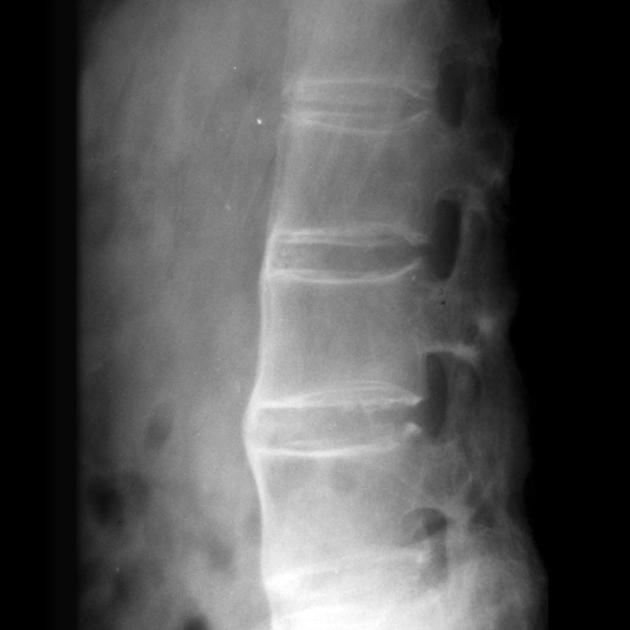

X光检查是最传统也是最基础的影像学检查方法

它的优点是简单、快速、费用低廉,几乎所有的医院都能够进行

在强直性脊柱炎的诊断中,X光主要观察骶髂关节和脊柱的改变

典型的改变包括:骶髂关节间隙变窄、关节面硬化、骨赘形成等

当疾病进展到后期时,X光还可以看到脊柱的"竹节样"改变,这是强直性脊柱炎的特征性表现

但是,X光检查也有明显的局限性

它只能发现已经发生的骨质改变,对于早期的软组织炎症和骨髓水肿是看不到的

这就像是只能看到房屋倒塌后的废墟,却看不到房屋倒塌前的裂缝一样